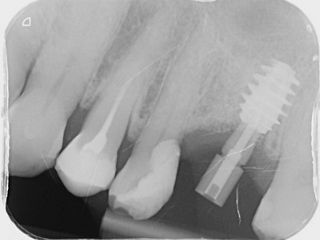

11a. 11b. Radiographs of the SSA in place and scan body for digital impressions.

11a

11b